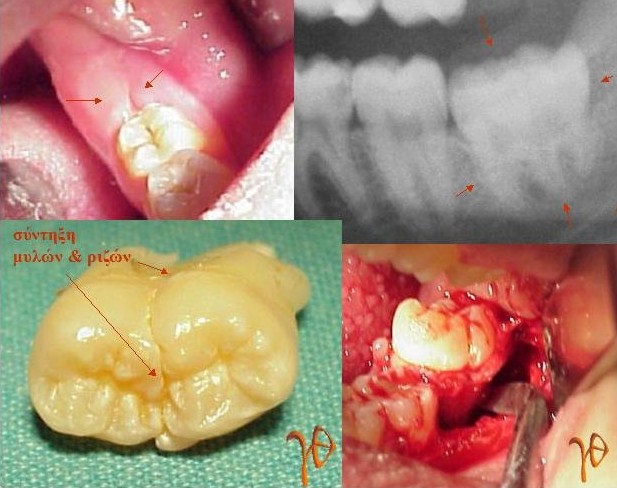

Δίδυμοι φρονιμίτες